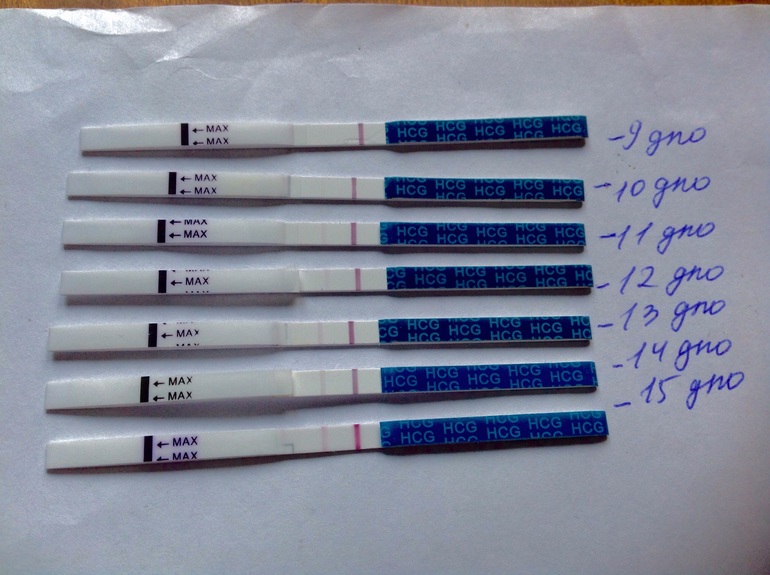

Где-то в глубине души я очень сильно надеялась, что с первого раза у нас получится. Я чувствовала это сердцем. Дальше тянулись мучительные дни ожидания. 1 дпо, 2 дпо, 3 дпо... На 9 дпо я все же не выдержала и мочканула тест))) Блин, пусто((( Никаких самых древних разваливающихся прадедов призраков( Терпение, только терпение! Тем временем, из "признаков", появившихся сразу же на 1 дпо, стала заболевшая правая грудь в районе подмышки. Ну, думаю, перед монстрами всегда болит за неделю где-то. Тянуло пару дней правый яичник, девочки на бб сказали, что ЖТ работает. А затем на 10 дпо под неведомым углом, тест показал блеееееедненький намек !!!! Сразу был сделан электронный Клеаблю, который показал "-"И до 15 дпо мои тест выглядели вот так.

Самые что ни на есть в полосочку. На 13 дпо я сдала хгч - 50, через 2 дня - 100, прогик где-то 15 был (все инвитро). Беременность есть, хгч растёт медленно, и я помчалась к гине. Она сделала УЗИ и нашла у меня плодное яйцо, да ещё поставила срок 4 недели! Это мне показалось очень странным, да и для поддержки прогика ничего не назначила. Через день у меня начал болеть живот как перед монстрами. Я с перепугу позвонила гине, она сказала принять дицинон. Ок. На следующий день начало мазать. Я помчалась уже у другой гине, она меня на кресло, и там из меня просто ливануло... Гиня очень грубо мне сказала: "Какая беременность, у тебя месячные". Ну, слава Богу, что все вышло само. Конечно, это был ужаснейший день. Я рыдала, муж приехал домой, и мы просто лежали молча, уткнувшись лицом в подушку... Но, время лечит...